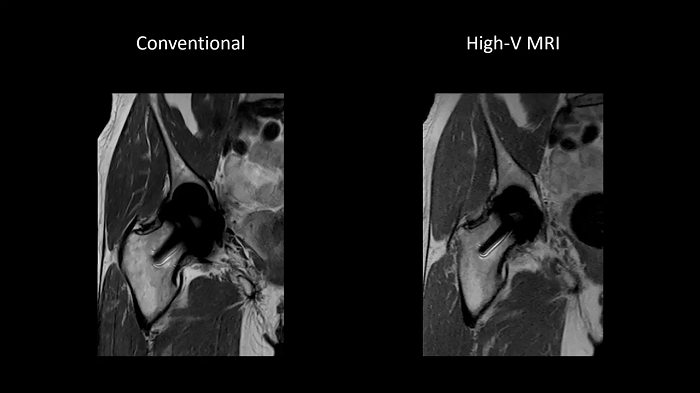

Improved implant imaging with High-V MRI

The imaging of metal implants has historically been difficult with conventional MRI systems as metal causes artifacts. High-V MRI offers intrinsic physical advantages that result in reduced metal distortions and strongly improved diagnostic capabilities for implant imaging.

Image Courtesy: University Hospital Erlangen, Germany | Image-ID: 1aaaa3623 | 4aaaa0399